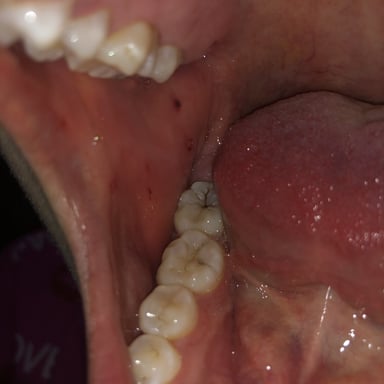

3. Triệu chứng của bệnh viêm niêm mạc miệng

Viêm niêm mạc miệng có rất nhiều triệu chứng khác nhau, có thể kể đến như:

– Nướu có tình trạng bóng, sưng hoặc đỏ.

– Xuất hiện các mảng trắng mềm hay mủ trên lưỡi.

– Có vết loét và chảy máu miệng.

– Khi ăn uống có cảm giác nóng nhẹ.

– Khi nói hay nuốt có cảm giác đau.